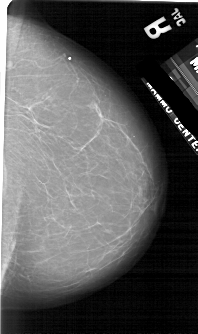

ics_version 1.0 filename A-1754-1 DATE_OF_STUDY 9 5 1996 PATIENT_AGE 59 FILM FILM_TYPE REGULAR DENSITY 1 DATE_DIGITIZED 16 3 1999 DIGITIZER HOWTEK 43.5 SEQUENCE LEFT_CC LINES 5491 PIXELS_PER_LINE 3556 BITS_PER_PIXEL 12 RESOLUTION 43.5 OVERLAY LEFT_MLO LINES 5341 PIXELS_PER_LINE 3361 BITS_PER_PIXEL 12 RESOLUTION 43.5 OVERLAY RIGHT_CC LINES 4996 PIXELS_PER_LINE 2956 BITS_PER_PIXEL 12 RESOLUTION 43.5 NON_OVERLAY RIGHT_MLO LINES 5281 PIXELS_PER_LINE 3226 BITS_PER_PIXEL 12 RESOLUTION 43.5 NON_OVERLAY |

FILE: A_1754_1.LEFT_CC.OVERLAY TOTAL_ABNORMALITIES 1 ABNORMALITY 1 LESION_TYPE MASS SHAPE ROUND MARGINS CIRCUMSCRIBED ASSESSMENT 3 SUBTLETY 4 PATHOLOGY BENIGN TOTAL_OUTLINES 1 BOUNDARY |